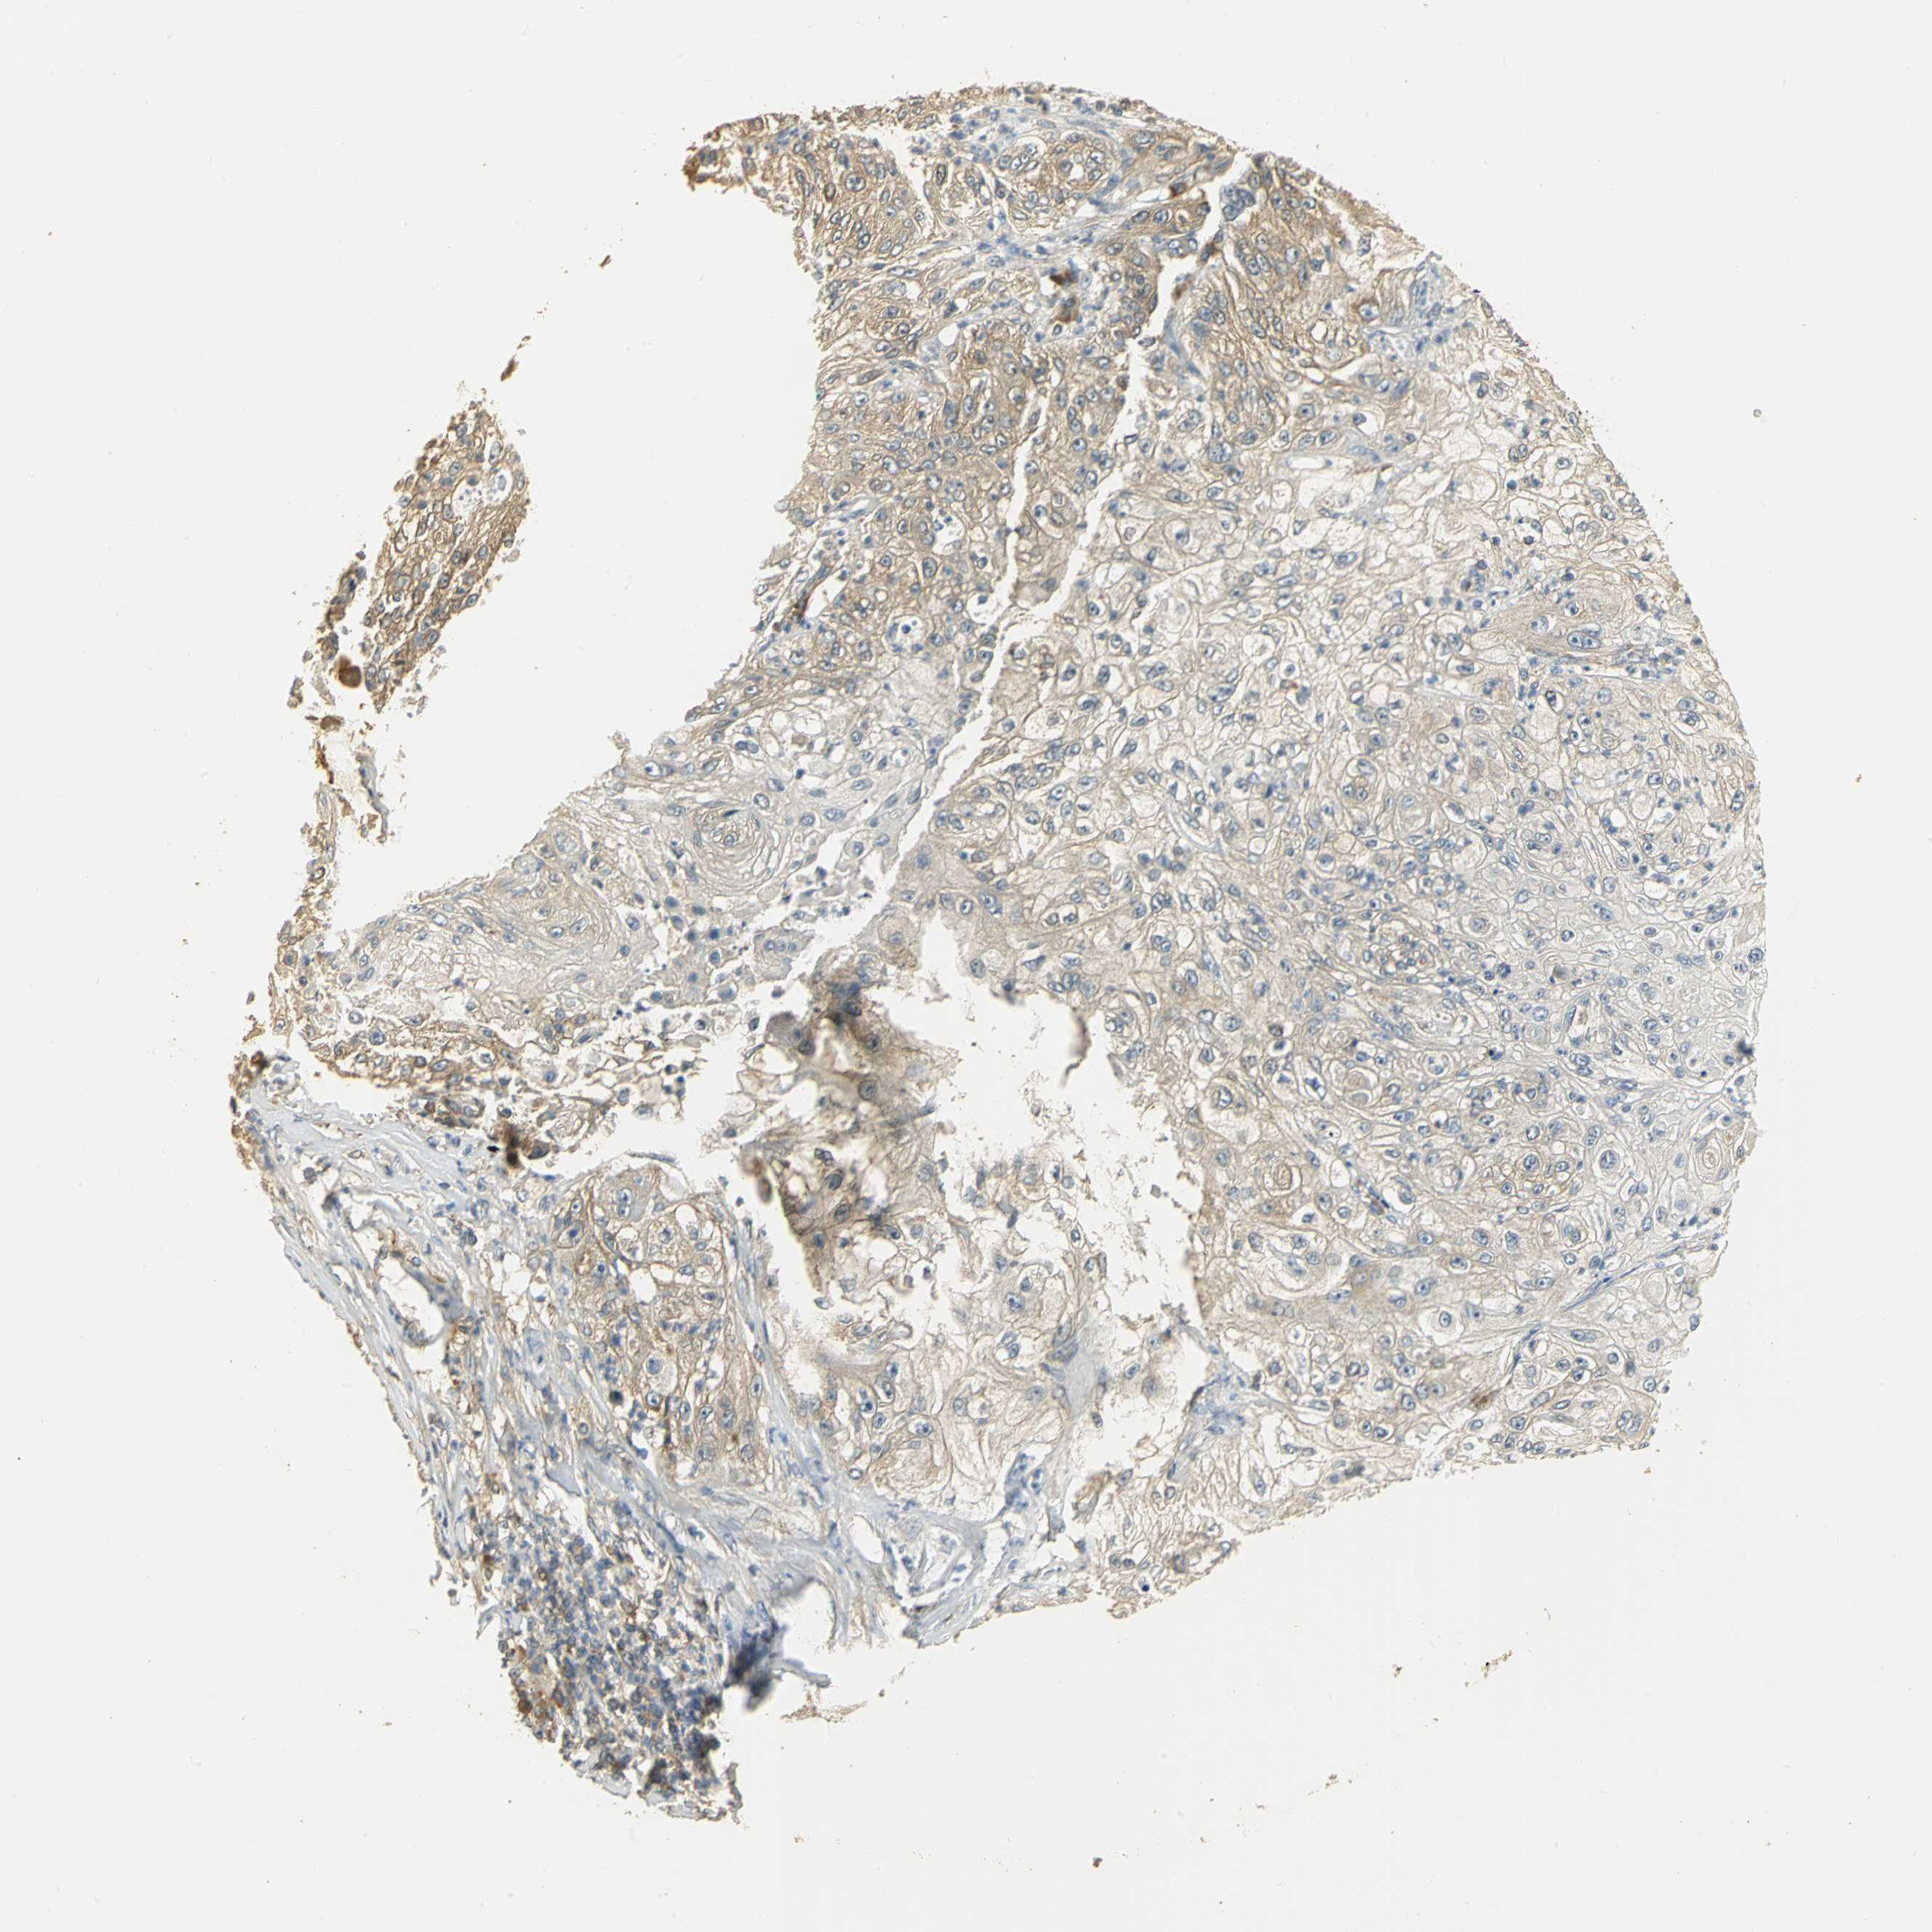

LUNG ADENOCARCINOMA (TCGA) - Interactive survival scatter ploti

The Survival Scatter plot shows the clinical status (i.e. dead or alive) for all individuals in the patient cohort, based on the same data that underlies the corresponding Kaplan-Meier plots. Patients that are alive at last time for follow-up are shown in blue and patients who have died during the study are shown in red.

The x-axis shows the expression levels (FPKM) of the investigated gene in the tumor tissue at the time of diagnosis. The y-axis shows the follow-up time after diagnosis (years). Both axes are complimented with kernel density curves demonstrating the data density over the axes. The top density plot shows the expression levels (FPKM) distribution among dead (red) and alive patients (blue). The right density plot shows the data density of the survived years of dead patients with high and low expression levels respectively, stratified using the cutoff indicated by the vertical dashed line through the Survival Scatter plot. This cutoff is automatically defined based on the FPKM cutoff that minimizes the p-score. The cutoff can be changed by dragging the vertical line or by entering a cutoff value in the square labeled "Current cut-off".

Under the Survival Scatter plot the p-score landscape (black curve; left axis) is shown together with dead median separation (red curve; right axis). Dead median separation is the difference in median mRNA expression between patients who have died with high and low expression, respectively. It is calculated as follows: median FPKM expression of dead patients with high expression - median FPKM expression of dead patients with low expression. This is intended to aid the user in visually exploring custom cutoffs and the associated p-scores and dead median separation.

Individual patient data is displayed and can be filtered by clicking on one or more of the category buttons on the top of the page. Categories describing expression level and patient information include: high, low, alive, dead, female, male and tumor stages. The scale of the x-axis can be toggled between linear and log-scale by clicking on the "x log" button. Mouse-over function shows TCGA ID, patient information and mRNA expression (FPKM) for each patient.

& Survival analysisi

Kaplan-Meier plots summarize results from analysis of correlation between mRNA expression level and patient survival. Patients were divided based on level of expression into one of the two groups "low" (under cut off) or "high" (over cut off). X-axis shows time for survival (years) and y-axis shows the probability of survival, where 1.0 corresponds to 100 percent.

RARS1 is not prognostic in Lung Adenocarcinoma (TCGA)

: 50.47

P scorei

N/A

Average pTPM 47.0

Number of samples 497